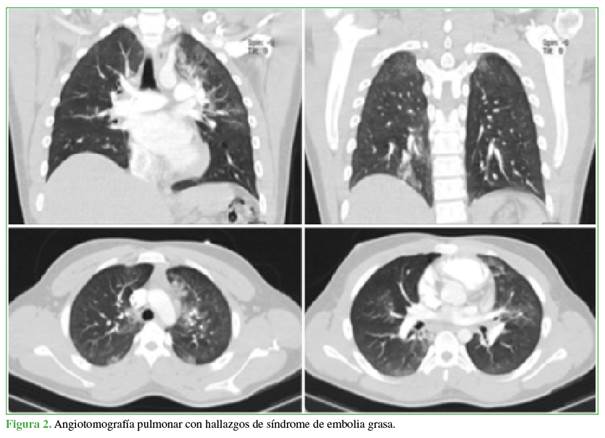

El mismo día, fue evaluado por los médicos de Medicina Interna quienes, ante el cuadro clínico, solicitaron una angiotomografía pulmonar. El informe oficial de Radiología descartó tromboembolismo pulmonar, focos consolidativos, contusiones, laceraciones pulmonares, neumotórax, derrame pleural o atelectasias, pero señaló opacidades en vidrio esmerilado, parcheadas, algunas de apariencia nodular, que comprometían principalmente los lóbulos superior izquierdo e inferior derecho y, en menor proporción, la región subpleural del ápice derecho que confirman la embolia grasa (Figura 2).

En la presentación de este caso, se muestra como solo con los síntomas respiratorios y el compromiso pulmonar manifestado por la hipoxemia progresiva hasta la insuficiencia respiratoria y los hallazgos en la angiotomografía se llega al diagnóstico de síndrome de embolia grasa.